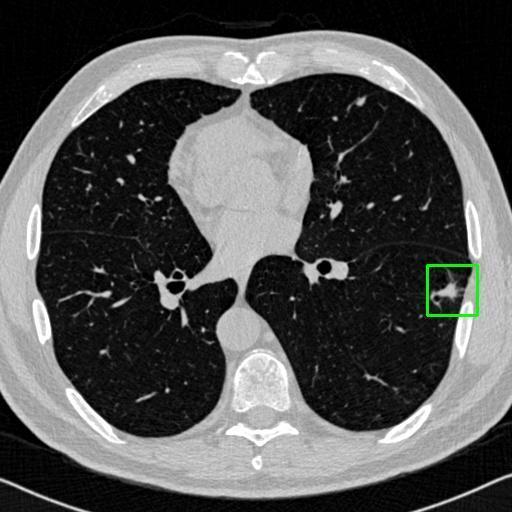

We developed an AI-based system using deep learning models for analyzing lung CT scans to detect and classify pulmonary nodules. We chose the YOLOv11 architecture for its enhanced object detection capability and adapted it specifically for medical imaging, incorporating pixel-level precision and severity classification.

Classification into three severity levels with colored bounding boxes.

Designed a severity classification system that categorizes nodules into null, moderate, and severe using colored bounding boxes, assisting in rapid clinical decision-making.